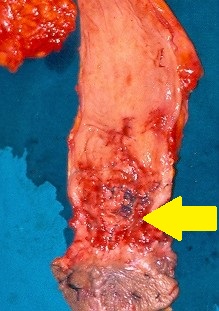

Αδενοκαρκίνωμα — Κοιλιοπερινεϊκή εκτομή ορθού. Κίτρινο βέλος — Εστία εκτομαθέντος νεοπλάσματος (Ευγενική παραχώρηση Dr. V. Penopoulos)